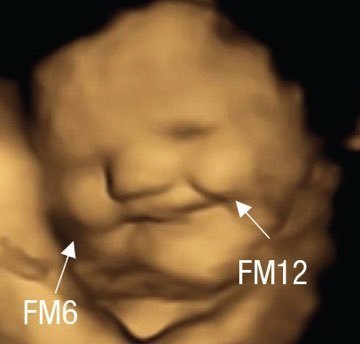

İlk fotoğraf anne lahana yedikten sonra fetusun 4 boyutlu ultrasonla görüntülenen yüzü, 2. fotoğraf anne havuç yedikten sonraki yüzü (32-36 haftalık gebelik). Anne karnındaki fetus lezzetleri algılıyor ve tepki veriyor. Bilim ❤️

İlk fotoğraf anne lahana yedikten sonra fetusun 4 boyutlu ultrasonla görüntülenen yüzü, 2. fotoğraf anne havuç yedikten sonraki yüzü (32-36 haftalık gebelik).

Anne karnındaki fetus lezzetleri algılıyor ve tepki veriyor.